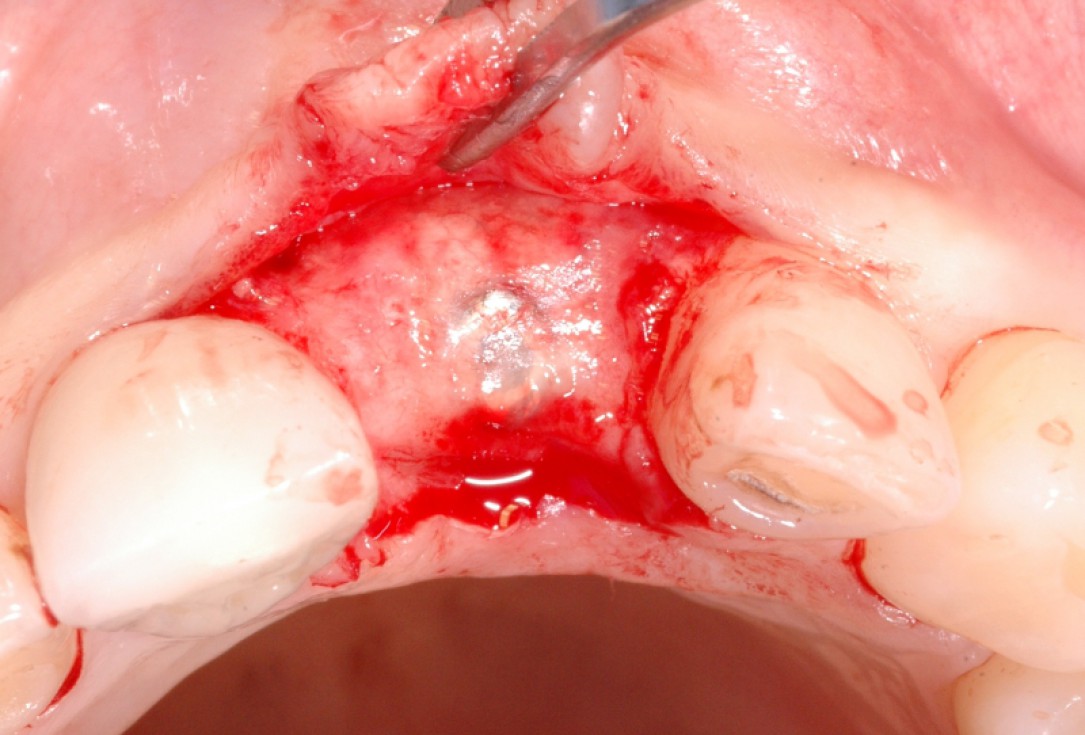

11/18 - Implant exposure and membrane removal 4 months post-operativeGBR together with soft tissue augmentation with mucoderm® and maxresorb® - Dr. S. Scherg